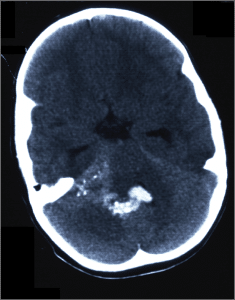

CT scan showing 4th ventricular ependymoma